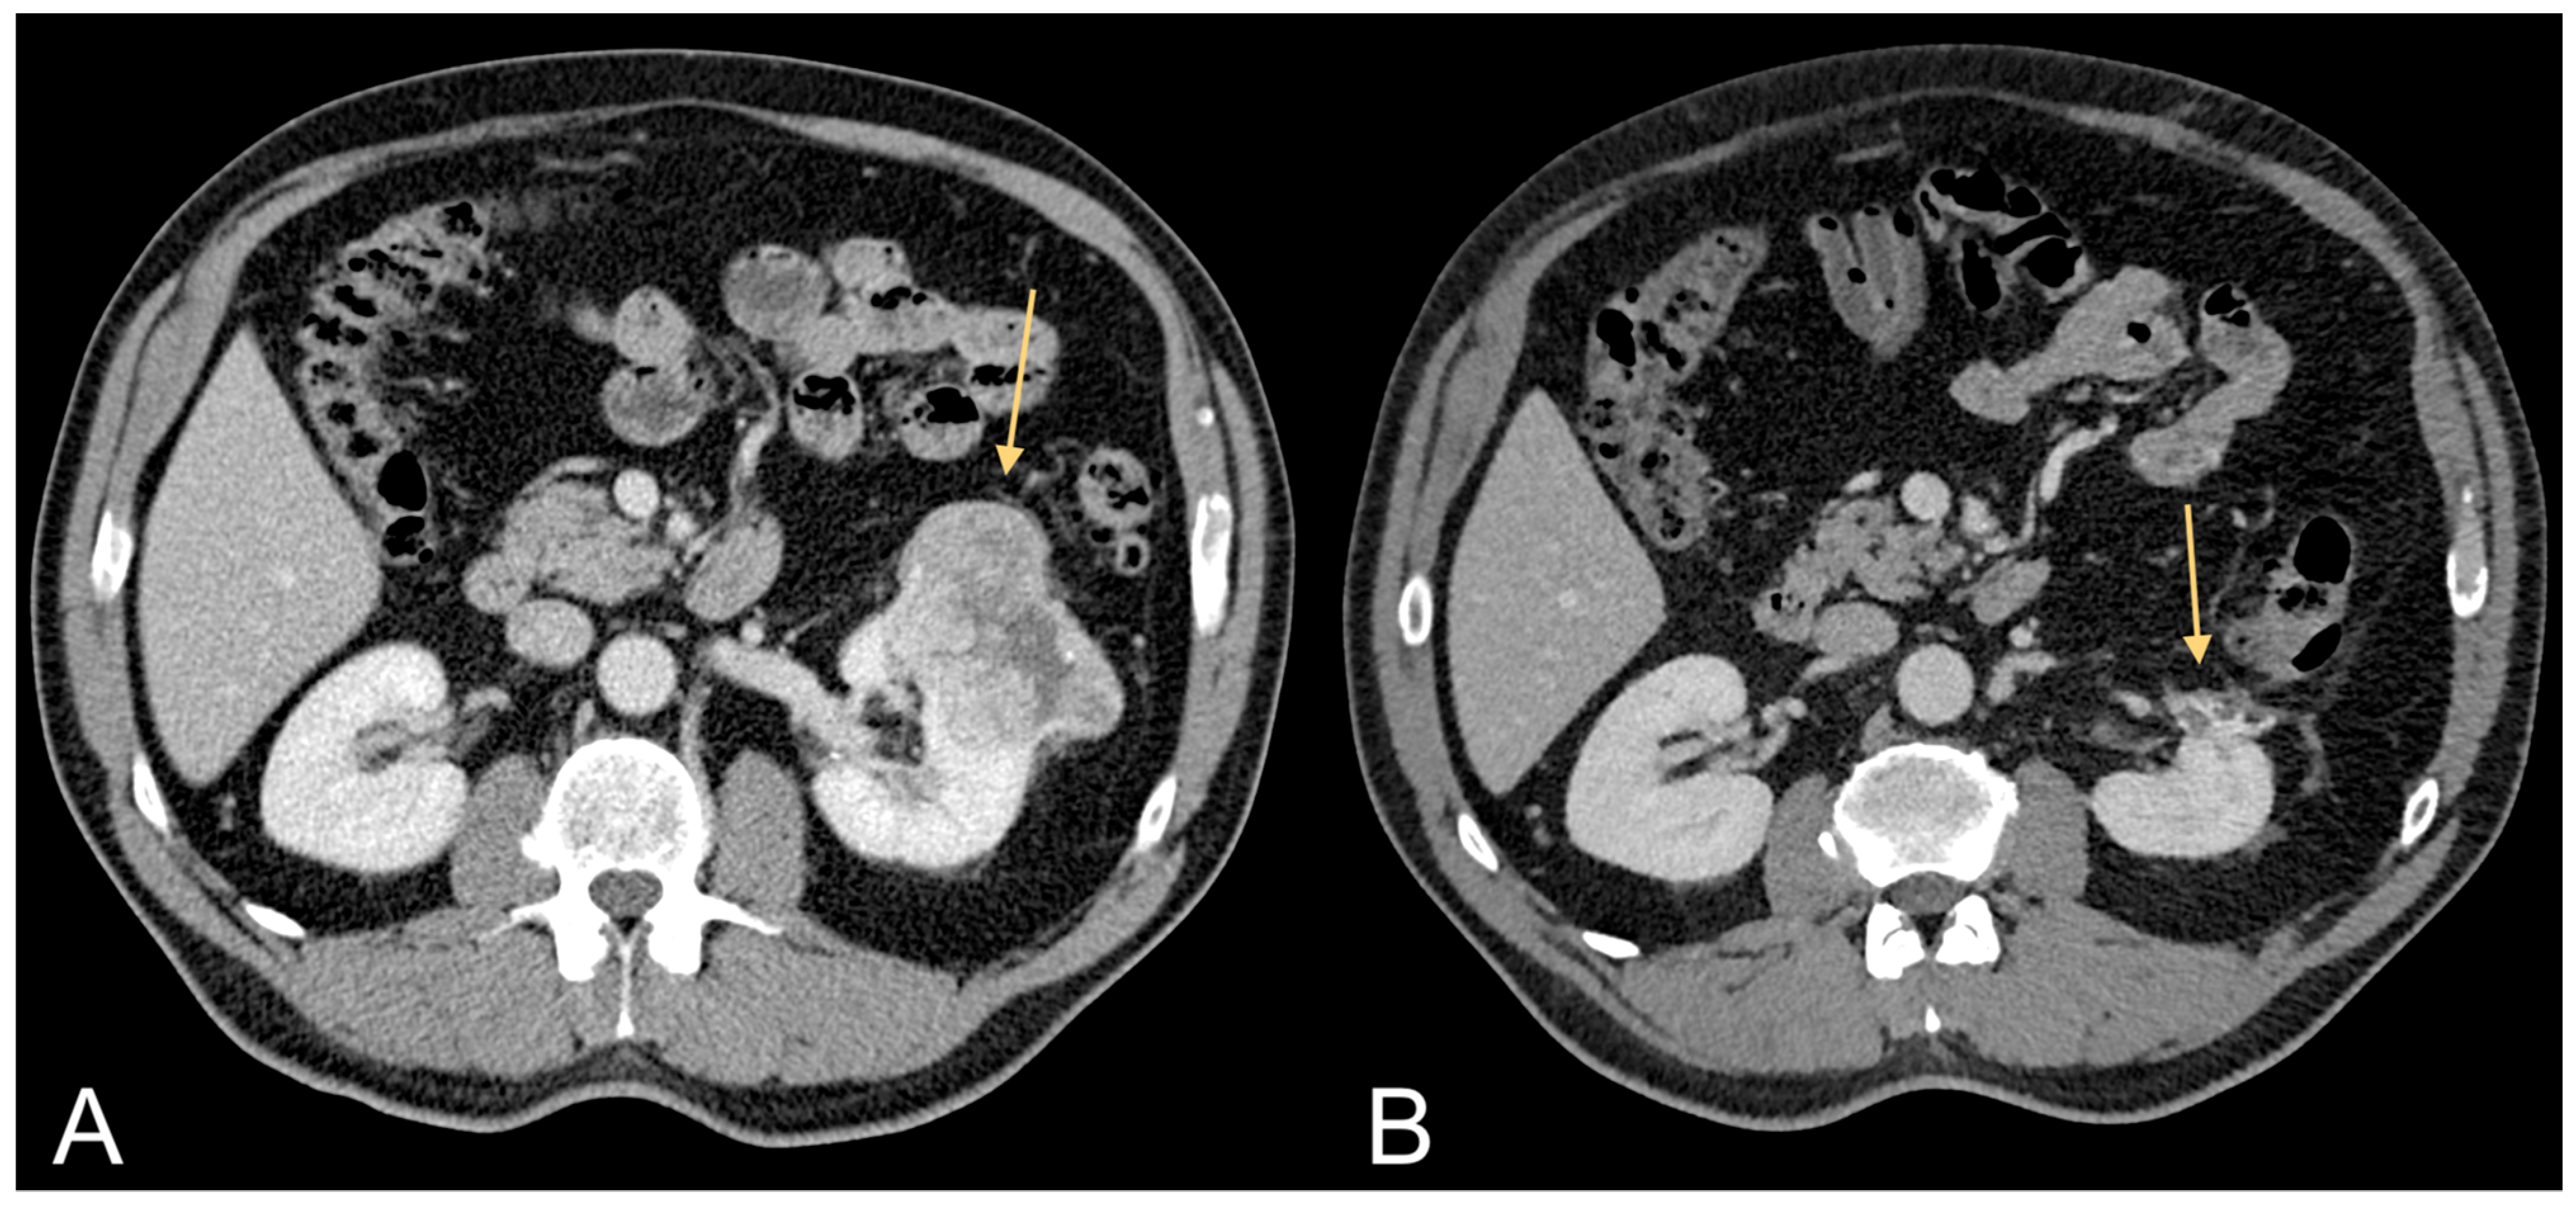

Figure 3.

Contrast-enhanced CT images of a 63-year-old male patient with excessive amount of VAT showing ccRCC (light orange arrow in (A)) and follow-up after tumorectomy (light orange arrow in (B)).